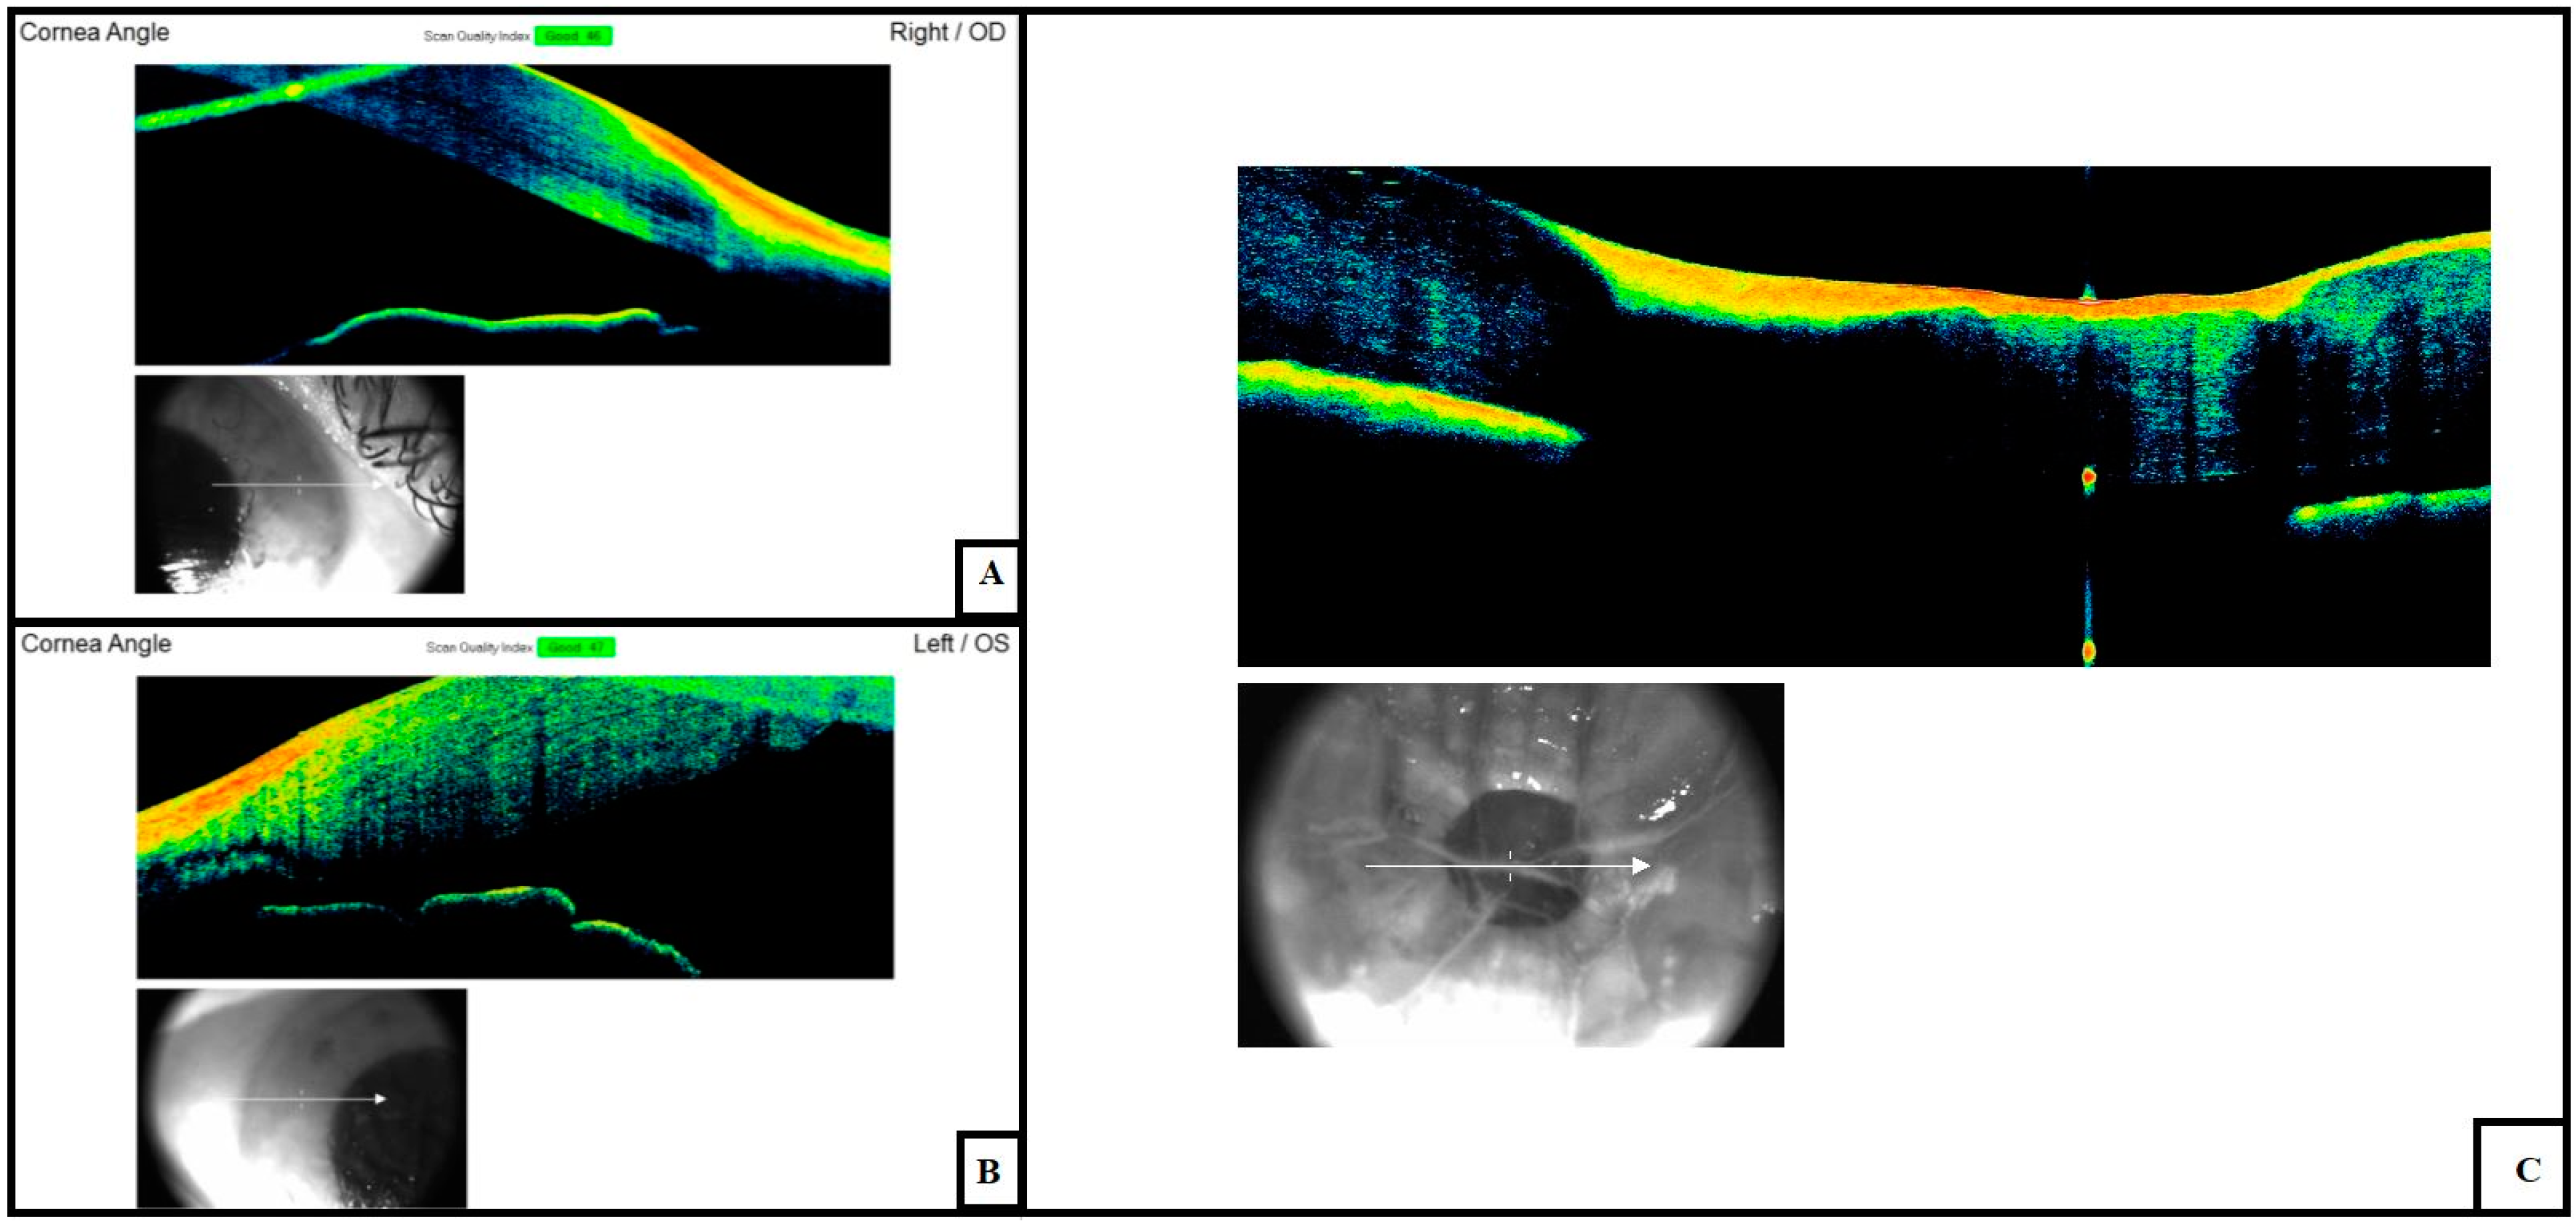

3.1. Cornea and Anterior Chamber